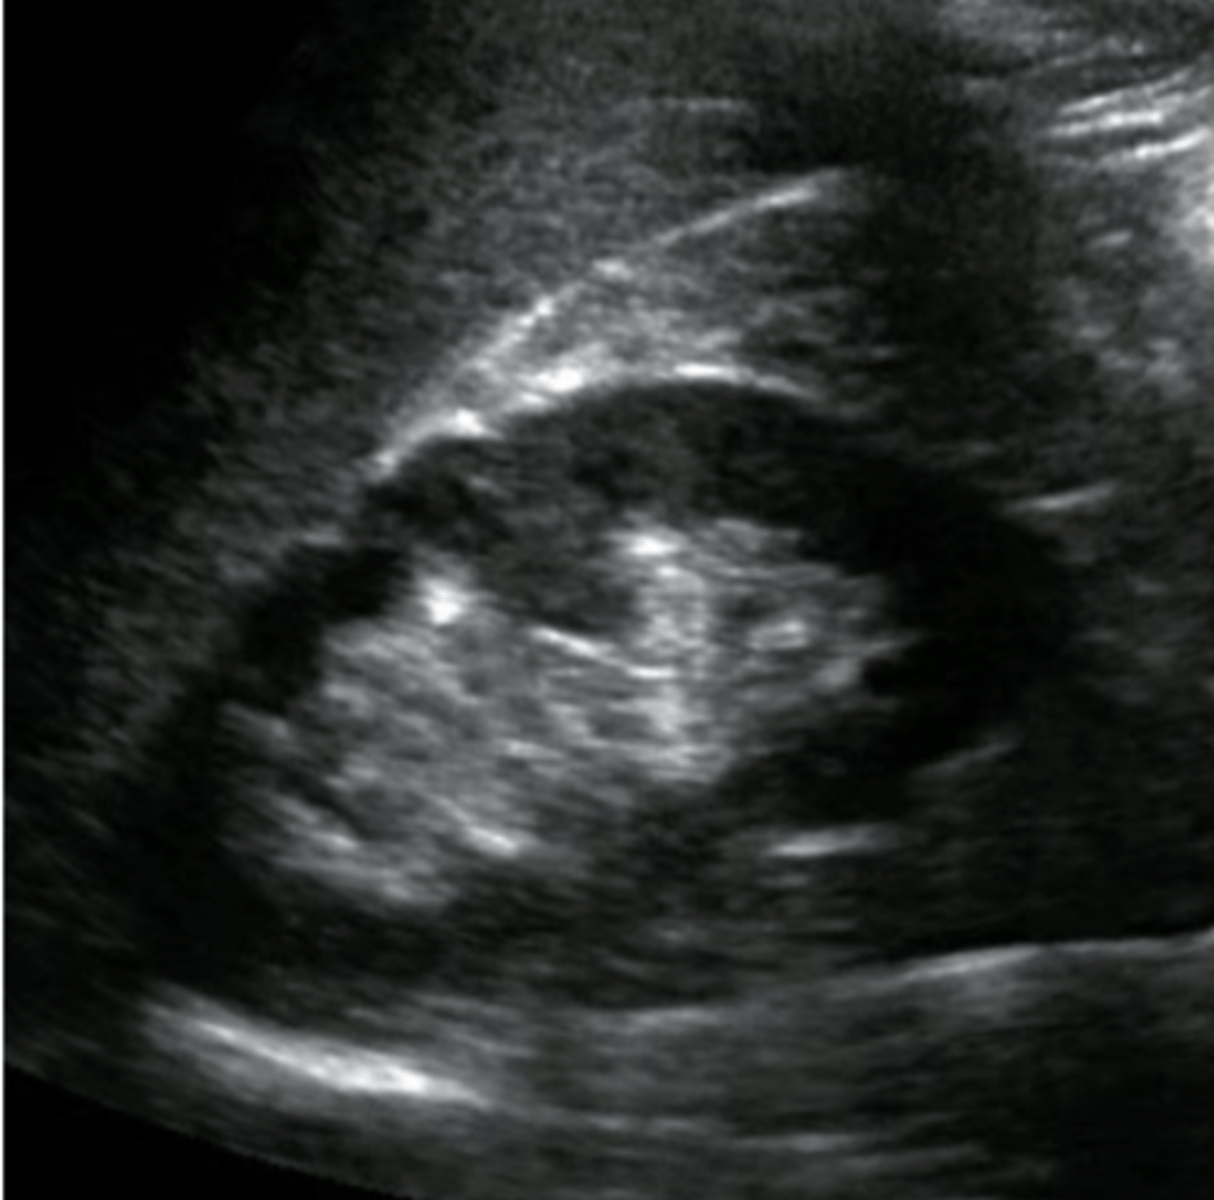

What normal variant of the kidney may mimic a renal mass or duplicated urinary system?

Hypertrophied Column of Bertin

Prominent folds of renal cortical tissue that protrude down into the medulla towards the renal sinus

Clearly separated from the renal sinus

Continguous with renal cortex

Echogenicity is the same as the cortex/renal parenchyma

Not over 3 cm in size as a rule